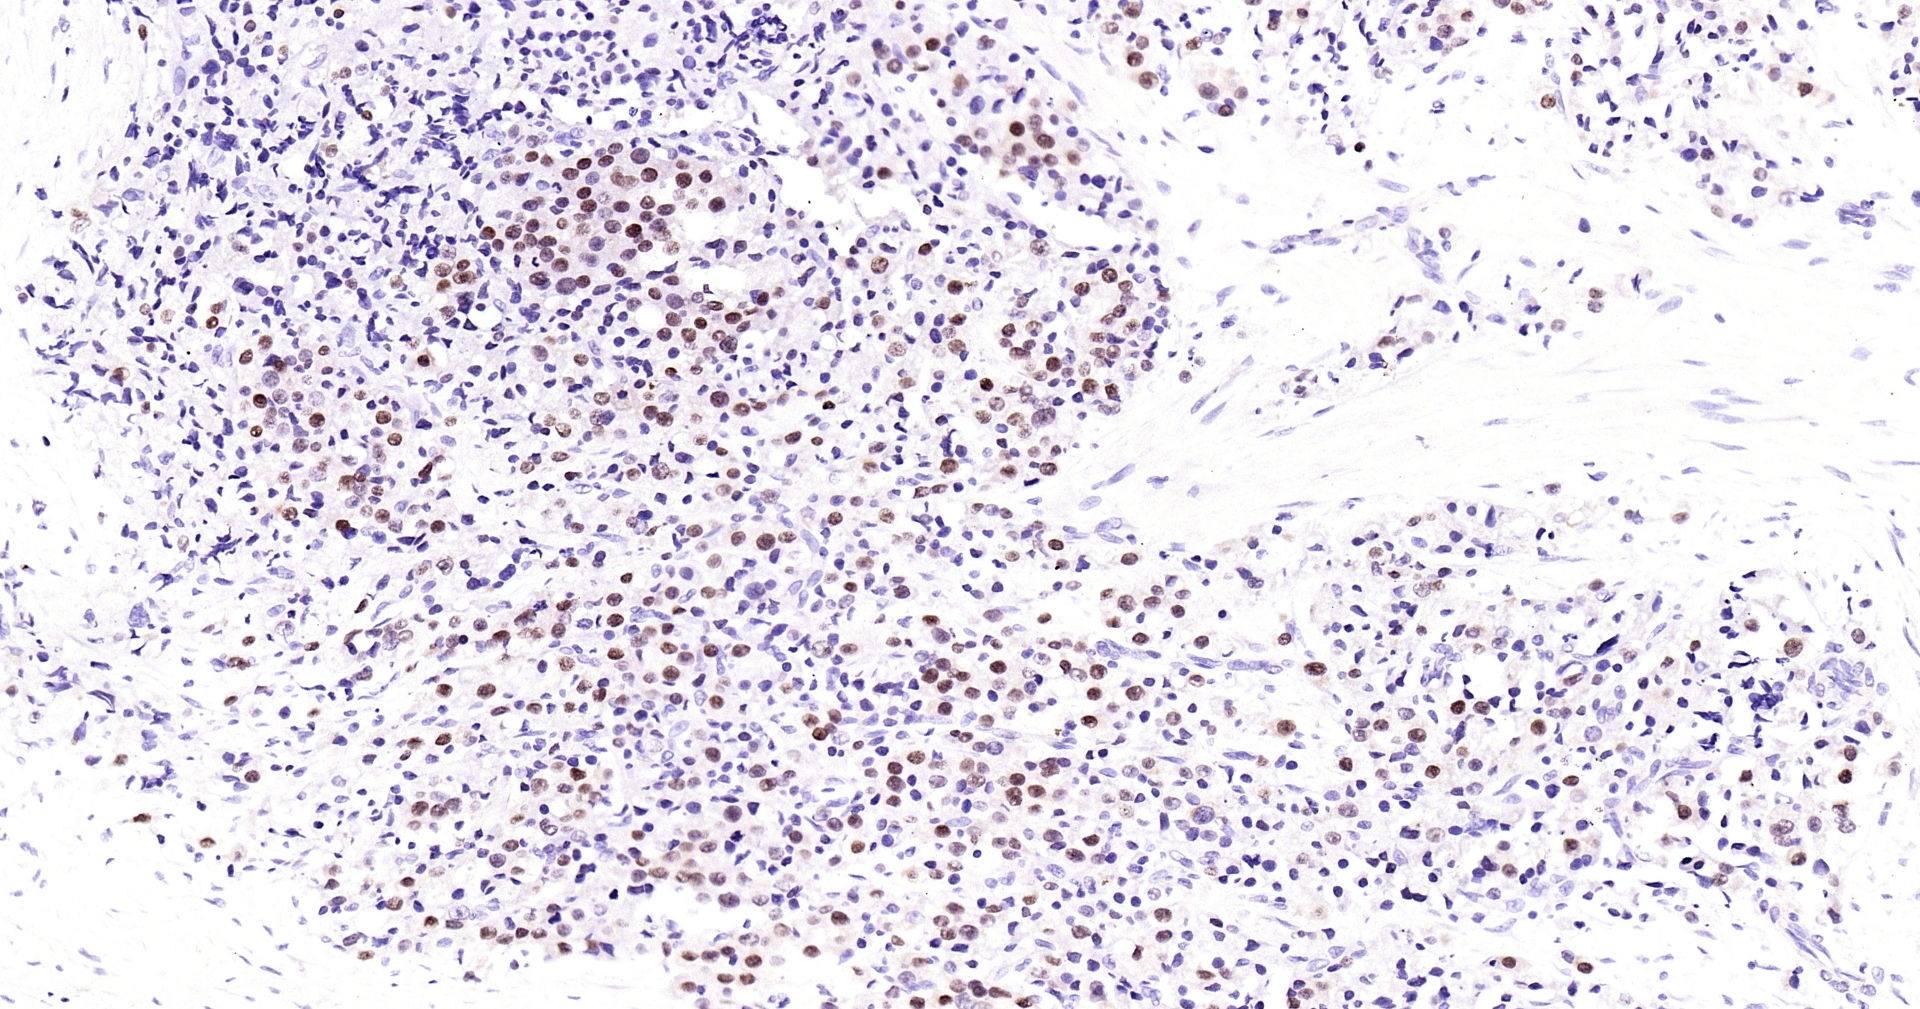

Androgen receptor Recombinant Antibody

• IHC-P

Product Name Androgen receptor Recombinant Antibody

Applications WB, IHC-P, IHC-F, IF(IHC-P)

IHC-P IHC-P1:50-200